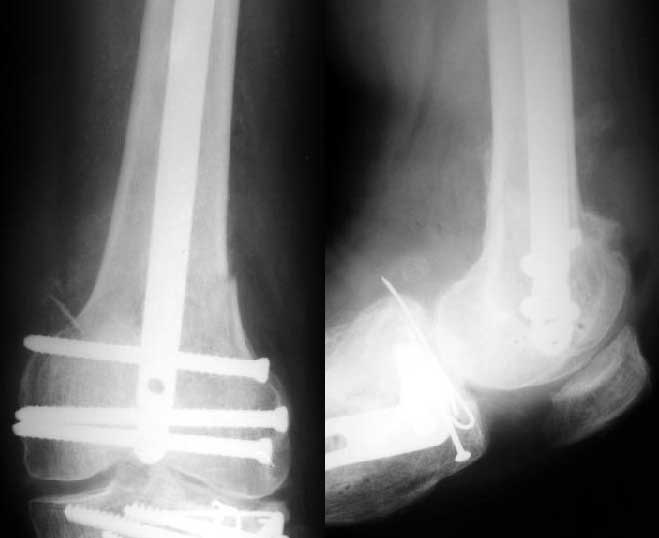

Sorry but I've just prepared postop images - attached. A solid 13 mm nail was used. A few degrees of recurvation appears to be which i missed on image intensifier. I'm still uncertain about

advantages/disadvantages of ante/retrograde nailing for such fractures.

The fixation as you have done is excellent. The locking screws on either side of the # are so apart. When we put in a supracondylar nail thro a keyhole incison in the knee, the locking bolts will be nearer the # and will be more stable allowing him to bear wt early. That was the reason the supracondylar nail was innovated. The locking is done by jig and no freehand method saving time.

the postop radiographs look excellent.

What do people think about driving an antegrade nail this distal as compared to retrograde nailing?